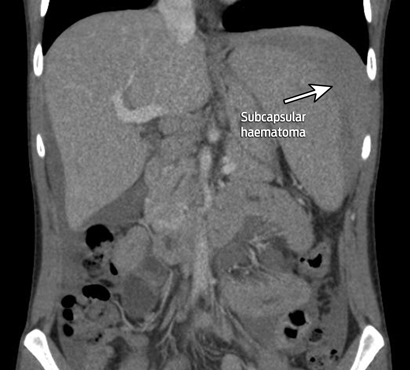

A contrast scan of the abdomen showed splenomegaly with subcapsular haematoma.